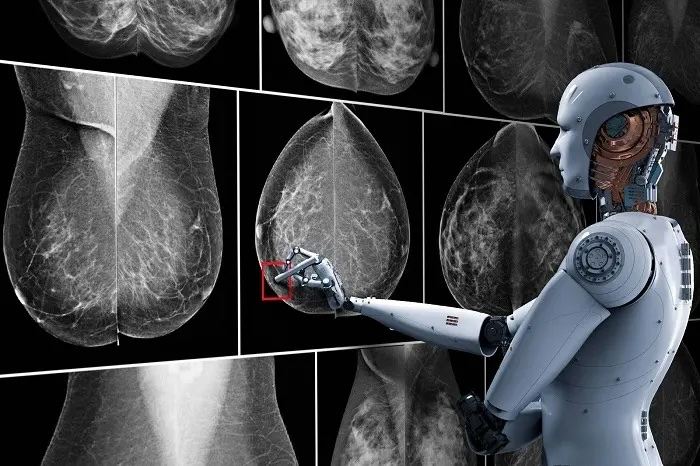

Einsatz von künstlicher Intelligenz

Hier kommt im Radiologischen Zentrum nun neuerdings künstliche Intelligenz zum Einsatz. Nach dem Motto "Vier Augen sehen mehr als zwei" werden die Aufnahmen auch von einer künstlichen Intelligenz beurteilt und dabei erkannte auffällige Befunde werden kenntlich gemacht. Letztlich entscheidet aber die Radiologin oder der Radiologe, die/der weitere Informationen aus der Vorgeschichte, den Tastbefund und die Ultraschalluntersuchung einbeziehen kann.

Wissenschaftliche Studien haben aber gezeigt, dass mit diesem Prinzip der KI-Zweitbefundung weniger krankhafte Befunde übersehen werden.